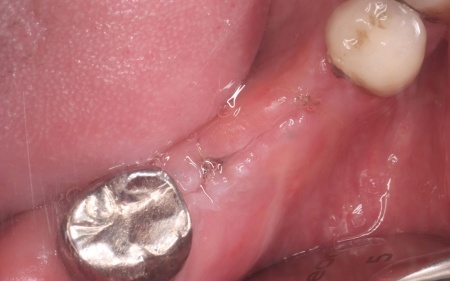

治療後